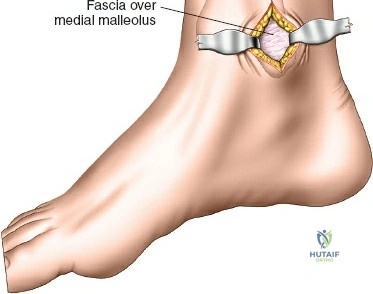

Incision Planning and Soft Tissue Dissection

- Incision Selection:

- Anteromedial Approach: Often preferred. A longitudinal incision, typically 3-5 cm, is made proximally and another similar incision distally (or a single longer incision) along the anteromedial aspect of the tibia. The proximal incision is placed away from the fracture zone and the distal incision is typically just proximal to the joint line, usually aligning with the non-articular part of the medial malleolus. The superficial peroneal nerve and saphenous nerve and vein must be identified and protected.

- Direct Anterior Approach: Can also be utilized, with incisions typically placed over the interval between the tibialis anterior and extensor hallucis longus muscles. The deep peroneal nerve and anterior tibial vessels lie deeper and must be protected.

- Subcutaneous Tunnel Creation: After skin incisions, subcutaneous dissection is performed to elevate skin flaps minimally. A submuscular or subcutaneous tunnel is then created, connecting the proximal and distal incisions. This tunnel should be just wide enough to accommodate the plate. Blunt dissection (e.g., using a blunt elevator, specialized plate insertion guide, or fingers) is critical to preserve the periosteum overlying the fracture fragments, which maintains their blood supply and vitality.

- Protection of Neurovascular Structures: Meticulous care must be taken to identify and protect superficial peroneal nerve branches (anterolateral aspect), saphenous nerve and vein (anteromedial aspect), and deep peroneal nerve and anterior tibial vessels (anterior compartment).